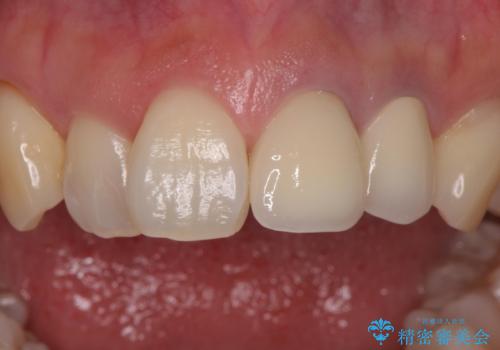

色調はクラウン修復により改善され、歯並びも術前より改善されたことで大変喜んでいただけました。